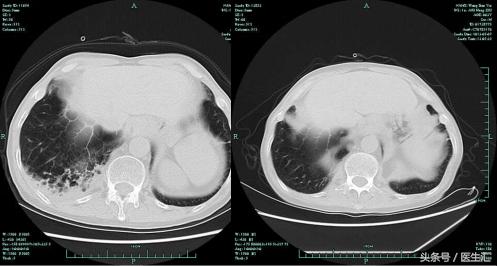

5.7病灶明显吸收复查肺部CT

患者体温正常,咳嗽气急好转,复查肺部CT右上肺及右下肺病灶吸收明显。考虑肺炎治疗有效,给予带口服抗生素出院。